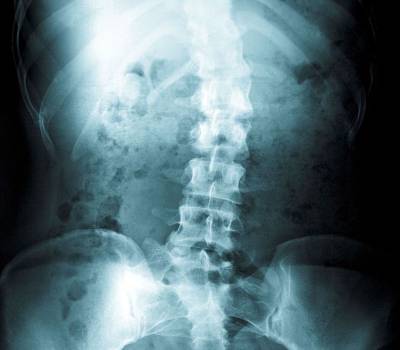

Es una deformidad de la columna vertebral que provoca una desviación de la misma, y que le da un aspecto de "S" o de "C", en vez de tener un aspecto de línea recta vista de frente. Además, es causante de un severo trastorno funcional y estético para el paciente, ya que puede provocar que los huesos de la columna giren haciendo que un hombro, un omóplato o una cadera queden más arriba en un lado que en el otro.